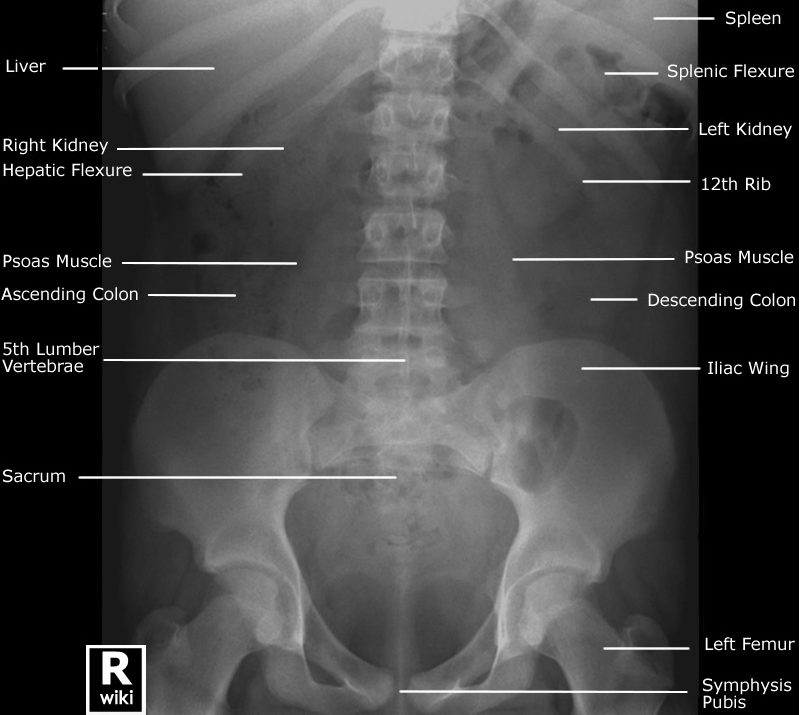

Label the viscera on the abdominal x-ray.